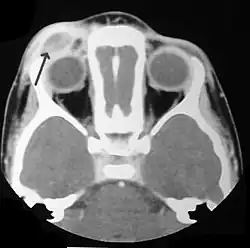

![]() Naciek tkanki okołogałkowej | |

- wytrzeszcz gałek ocznych (jedno- lub obustronny)